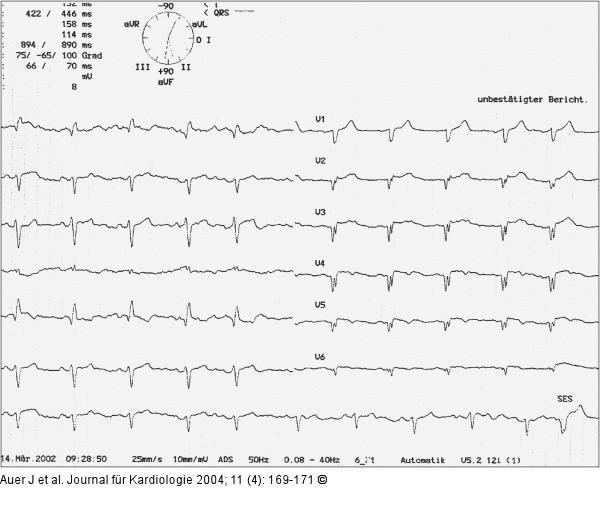

Abbildung 5: Akutes Koronarsyndrom - Stenose der linken Herzkranzarterie EKG 4 Stunden nach Stent |

Abbildung 5: Akutes Koronarsyndrom - Stenose der linken Herzkranzarterie

EKG 4 Stunden nach Stent |